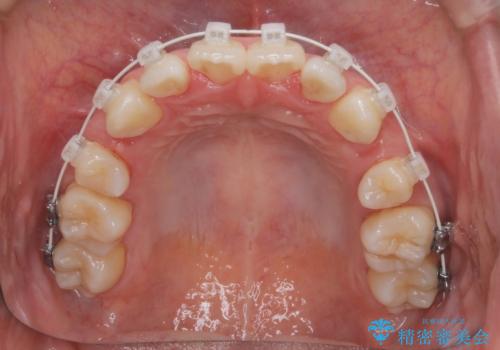

【審美装置】前歯のデコボコを綺麗に

- 上の前歯のデコボコが気になるということで来院されました。

叢生量(デコボコ)が多いため、上下左右4番目の歯を抜歯してワイヤー矯正を行う治療計画を立てました。

主訴である前歯のデコボコが改善され、噛みあわせも綺麗になりました。

歯肉退縮もなく、予定通りに治療を終えることができ良かったです。